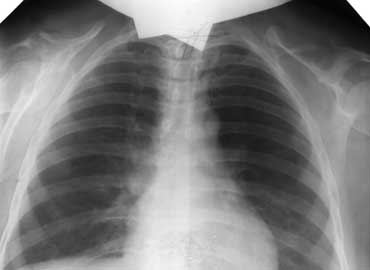

Рисунок. Черепно-ключичный дизостоз - наследуемое по аутосомно-доминантному типу заболевание, для которого характерно частичное (имеется только акромиальный отдел или ключица фрагментирована) или реже (10%) полное отсутствие ключиц. Лопатки уменьшены в размерах. Изменён череп: увеличена мозговая и уменьшена лицевая части, большой родничок может оставаться открытым в течение всей жизни. Верхняя челюсть с придаточными пазухами недоразвиты. Характерно запоздалое и несовершенное развитие постоянных зубов (молочные зубы задерживаются до 25-30 лет). Иногда не срастаются дужки позвонков.

Больная С., 50 лет. На прямой рентгенограмме грудной клетки видно полное отсутствие ключиц с двух сторон, гипоплазия и деформация лопаток.